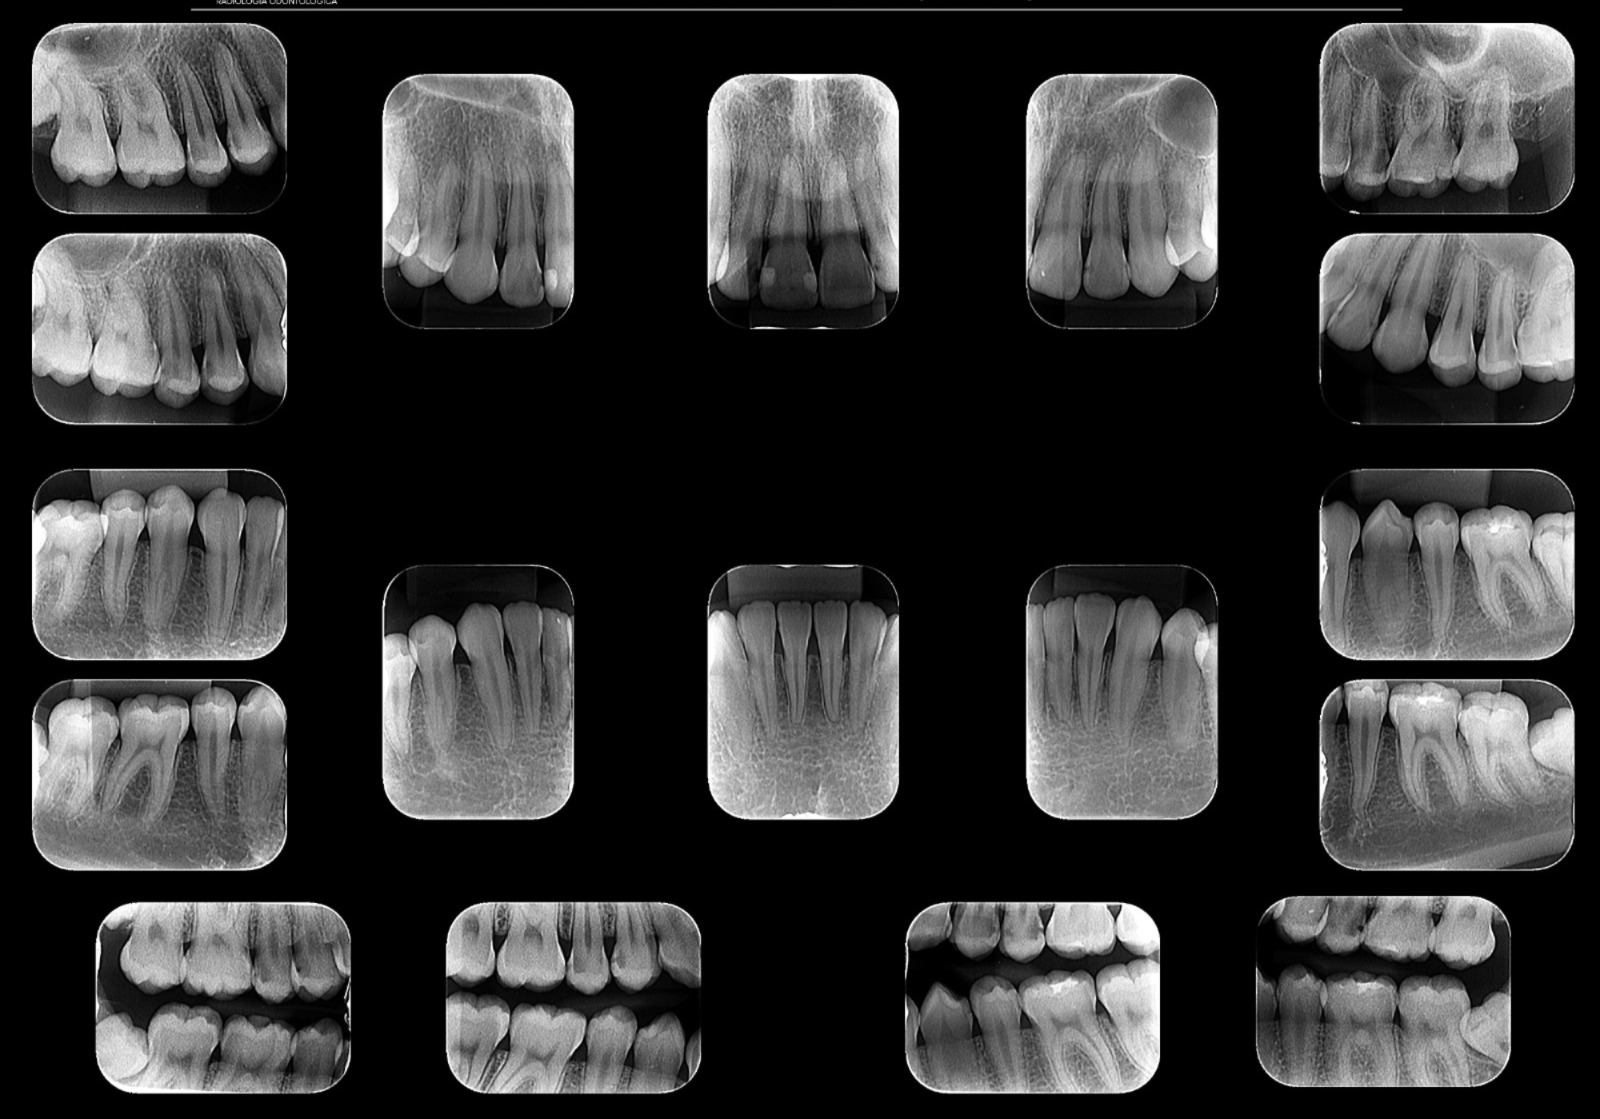

Periapical / Interproximal

Foco em um ou poucos dentes. Mostra desde a raiz até a coroa. Usado para detectar cáries e infecções.